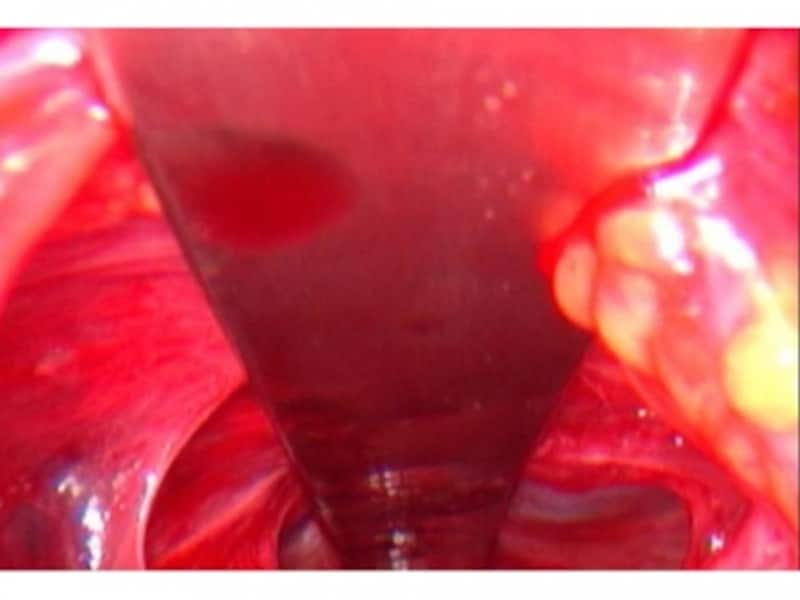

次に反対側の胸壁から、スチールバーとよばれる湾曲した太い金属の太い棒の先端を入れ、先程の鉗子の先端でつまみ、鉗子を手前に引っ張り、スチールバーを反対側の胸壁から胸骨の下を通し、手前の胸壁まで誘導します。

反対側から手前の胸壁まで誘導されたスチールバー。

このカーブしたスチールバーを180度回転させると、陥凹した胸骨が下の金属に押し出されて、胸郭全体の形が矯正されます。

180度回転したスチールバー。胸骨が前に押し出されます。